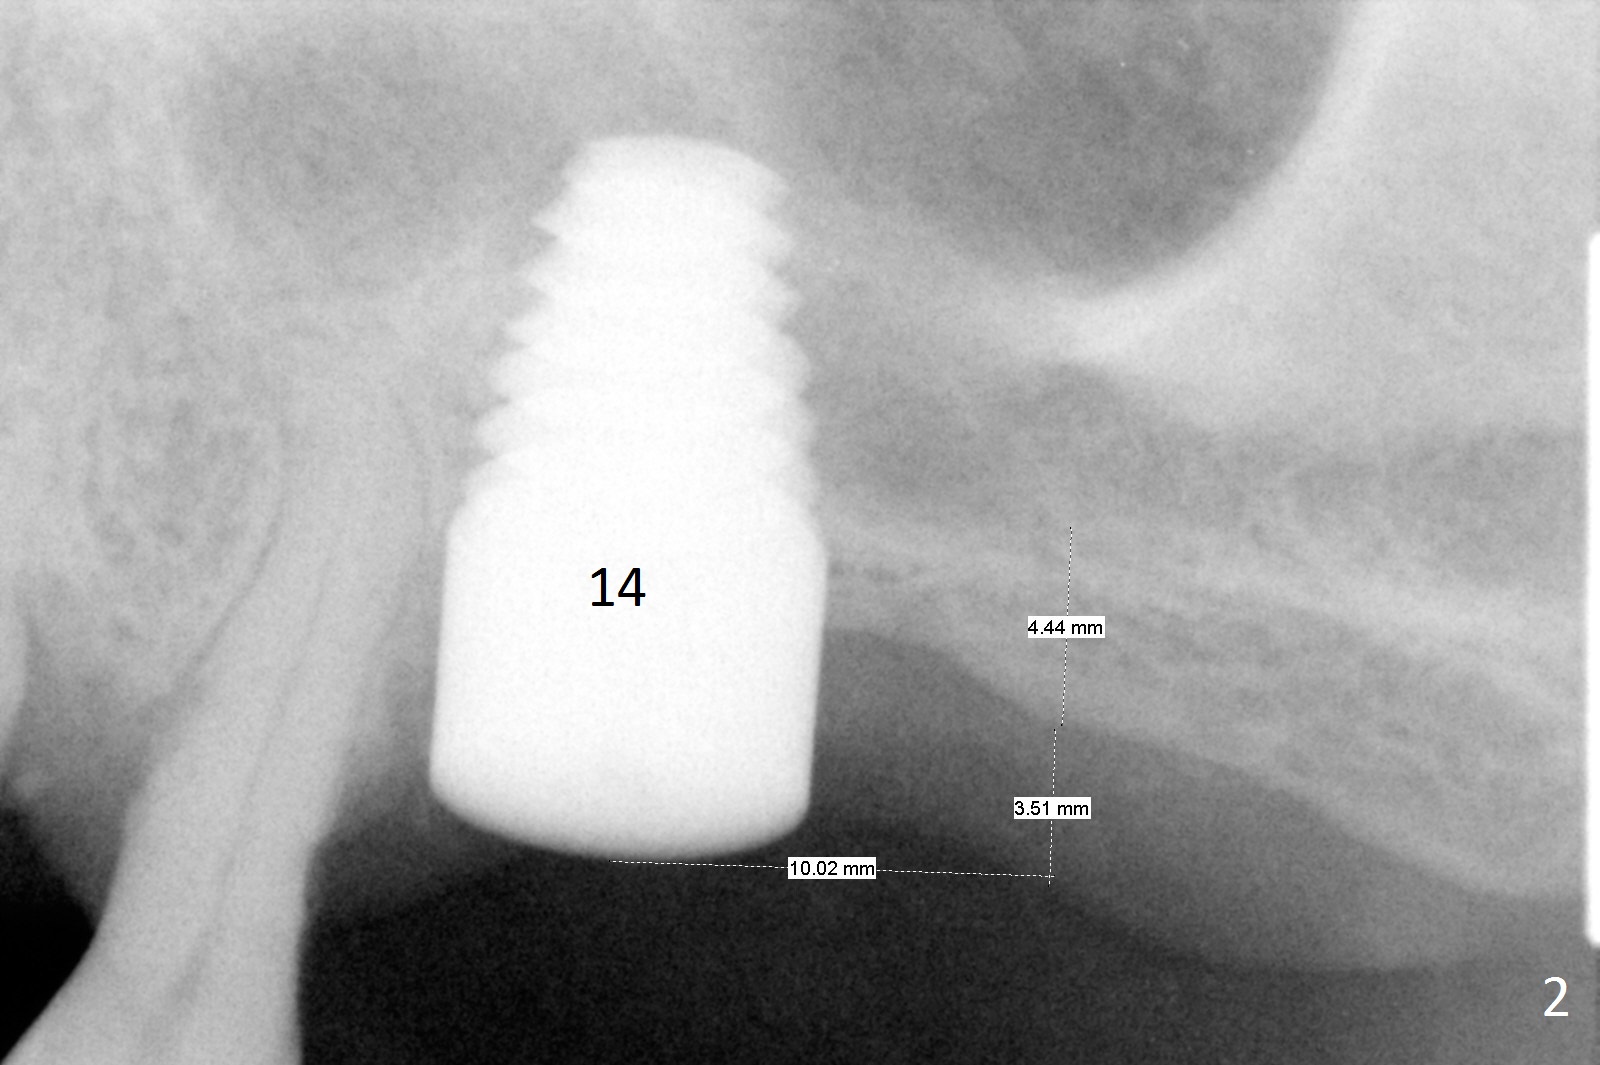

A 58-year-old man has two types of implant complications: periimplantitis at #4 (in spite of 2 bone graft surgeries, Fig.1) and abutment loosening at #14 and repeatedly 19 (probably due to bruxism, Fig.2,3).

To overcome bruxism, implants will be placed at the 2nd molar sites (total 4). Since the implant at #19 was placed distal, the crowns at #18 and 19 will be splinted. The unipost at #14 is 6 mm, 10º cemented with Ketac (implant 8x14 mm). To increase retention, use bonding and place 1 or 2 heavy retention grooves or use a straight abutment. If the existing abutment cannot be removed, enlarge the retention groove and bury a piece of wire in the groove with bonding. The last resort will be splinting with #15.